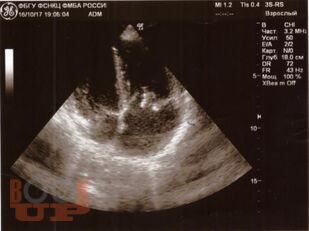

Инфекционный эндокардит

В настоящем учебном пособии освещены вопросы современных представлений об инфекционном эндокардите: определение, классификации, основные принципы диагностики и лечения. Имеются тестовые задания и ситуационные задачи для самоконтроля знаний.